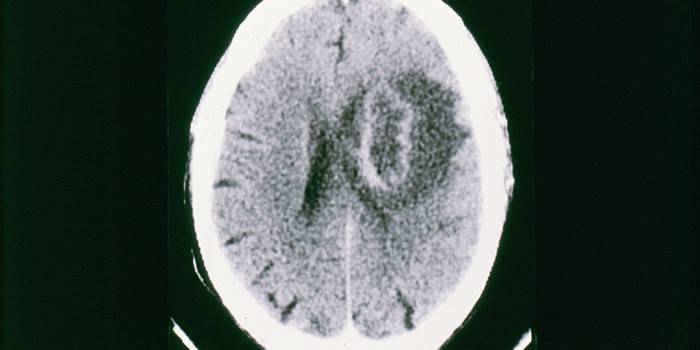

Jedną z najniebezpieczniejszych chorób powodowanych przez pierwotniaki jest malaria. Zakażenie następuje przez kontakt ze śliną komara, objawy pojawiają się tydzień po zakażeniu.Malaria często zaczyna się od ciężkiego przebiegu, ze wzrostem temperatury do 40-41 stopni, silnym bólem głowy, zaburzeniami rytmu serca, dusznością, niedokrwistością. Po zakończeniu ataku osoba obficie się poci, temperatura spada, stan poprawia się do następnego nawrotu. Nieleczona i leczona choroba może prowadzić do malarii mózgowej i śmierci.